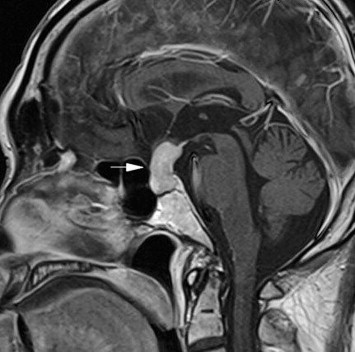

A man aged 66 years presented with nausea, vomiting, poor appetite, and body weight loss of 4 kilograms in 1 month. He had a history of acute cholecystitis status postcholecystectomy and chronic hypertrophic rhinitis. Anorexia and fatigue were also noted. His condition did not improve after he asked help from the Show Chwan Memorial Hospital Changhua, Taiwan and a postmediastinal mass with diffuse mediastinal lymph node enlargement was revealed by chest computed tomography (CT) scan. Then, he was transferred to our hospital. Physical examination revealed no specific findings. The chest CT scan demonstrated a 2.4-cm nodule in the right middle lobe abutting the right pericardial pleura and an infiltrating right-posterior mediastinal and paraspinal masses with pleural extension (Fig. 1A). No extension to bone or intraspinal canals was noted. There were multiple mediastinal lymph node enlargements, with the largest being a diameter of about 17 mm in the aortopulmonary window (AP) window region. In addition, bilateral infiltrating masses were noted in the upper kidney level (Fig. 1B). The stomach also demonstrated focal thickening of the wall over the lesser curvature side.

(A) Infiltrating right posterior mediastinal and paraspinal masses with pleural extension; (B) bilateral infiltrating masses in both kidneys; (C) after steroid treatment, there was a significant decrease in the size of the previously noted nodule in the posterior mediastinal and right paraspinal masses, (D) as well as in the prior infiltrating masses in both kidneys.

After the operation, the patient kept taking 5 mg of prednisolone every 2 days for 3 months and a follow-up CT scan revealed a significant decrease in the size of the previously noted nodule in right middle lobe, posterior mediastinal and right paraspinal masses (Fig. 1C) and prior infiltrating masses in both kidneys (Fig. 1D).